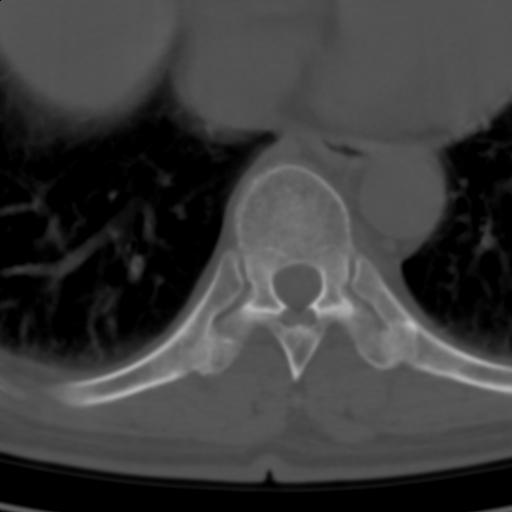

标题: CT25189:胸椎ct,请会诊!

既往食管癌,现行ct检查!

中上段食道癌,椎体轻度退变。

支持中上段食道癌,椎体轻度退变,必要时做ect。